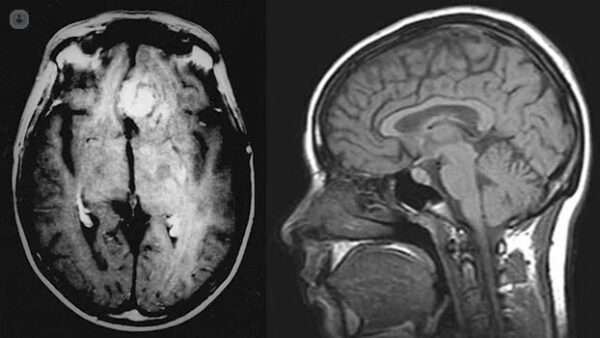

La resonancia magnética con realce de gadolinio es el método preferido para detectar las lesiones intracraneales y definir su ubicación, forma y tamaño. Además, permite evaluar la extensión de la distorsión de la anatomía normal, así como el grado de edema cerebral asociado o efecto de masa. Este procedimiento es extremadamente útil para proporcionar una imagen precisa de los tumores, ya que las secuencias de imagen pueden resaltar detalles finos y ofrecer una visión clara de la estructura cerebral afectada. El contraste con gadolinio mejora la visualización de las lesiones, haciendo que los bordes tumorales sean más nítidos y permitiendo la distinción entre el tejido tumoral y las estructuras circundantes. Esta técnica es particularmente ventajosa para detectar tumores en áreas difíciles de evaluar, como la fosa posterior del cráneo.

Aunque la tomografía computarizada (TC) con realce de radiocontraste también puede realizarse en algunos casos, es generalmente menos útil que la resonancia magnética para detectar lesiones pequeñas o tumores en la fosa posterior. La TC es más sensible para la evaluación de la calcificación ósea y la presencia de hemorragias, pero no ofrece la misma claridad y detalle que la resonancia magnética en cuanto a la definición de los márgenes tumorales o la evaluación de la distorsión anatómica.

El aspecto característico de los meningiomas en las imágenes de resonancia magnética o tomografía computarizada es casi diagnóstico, ya que estos tumores tienden a localizarse en sitios típicos, como las regiones parasagital y silviana, el surco olfatorio, la cresta esfenoidal y el tubérculo selar. En las imágenes sin contraste, los meningiomas se presentan como una zona homogénea de mayor densidad, que se realza uniformemente con el contraste. Este patrón de realce es un marcador distintivo, lo que facilita su diagnóstico sin necesidad de procedimientos invasivos adicionales.

En cuanto a los gliomas, hay secuencias adicionales de resonancia magnética que pueden ser útiles para diferenciarlos de otras patologías intracraneales. La imagen por perfusión, la espectroscopía por resonancia magnética y la imagen ponderada por difusión son algunas de las herramientas que pueden proporcionar información adicional sobre la vascularización, la composición bioquímica y el comportamiento celular del tumor. Sin embargo, ninguna de estas técnicas es lo suficientemente específica como para eliminar la necesidad de un muestreo de tejido, ya que un diagnóstico definitivo generalmente requiere la confirmación histológica obtenida mediante biopsia.